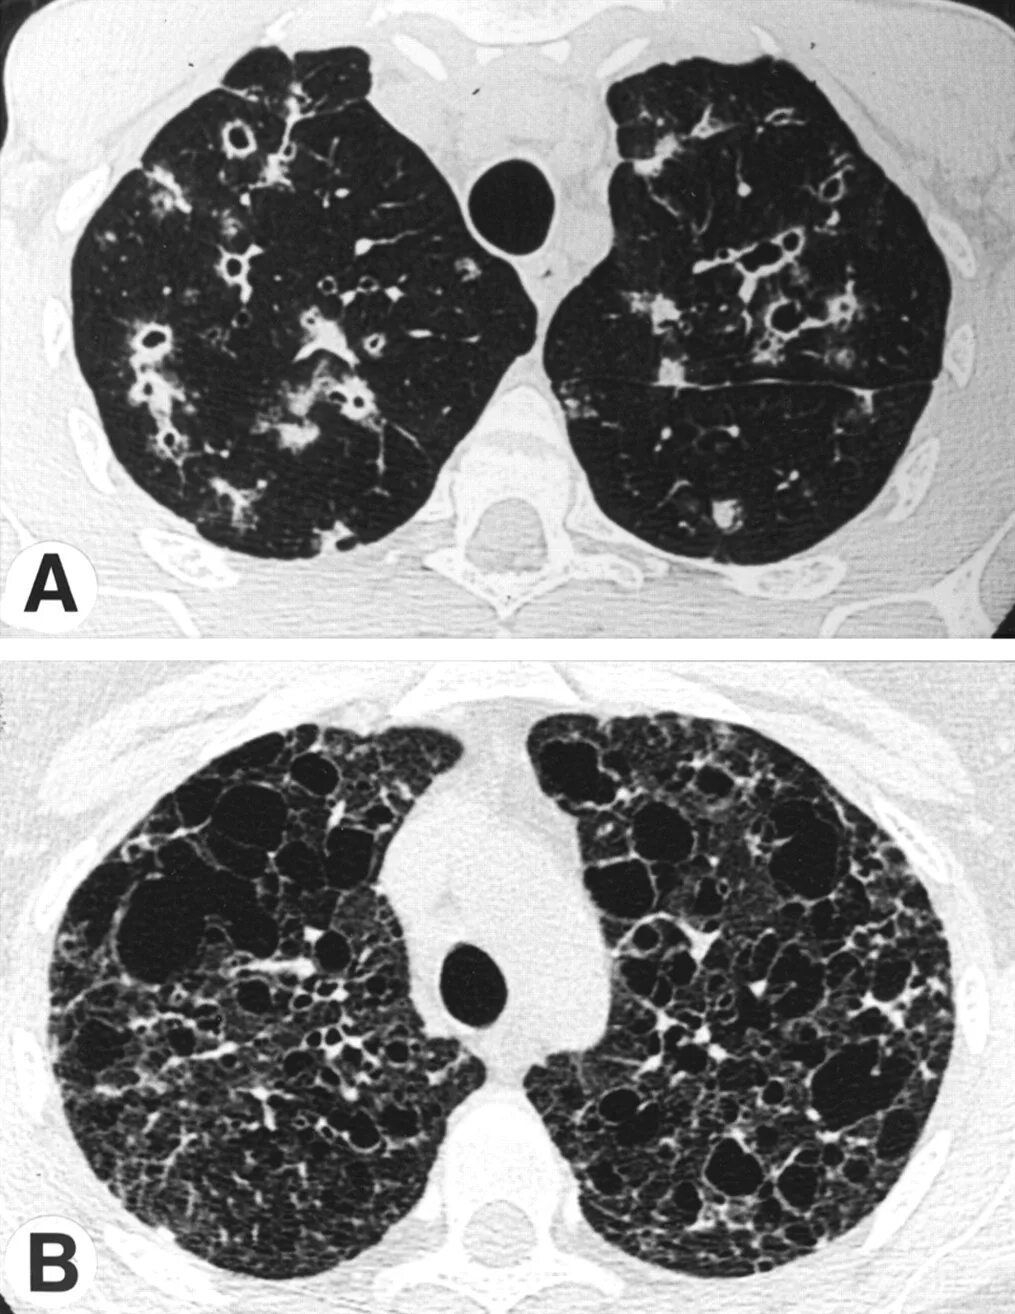

Кт х